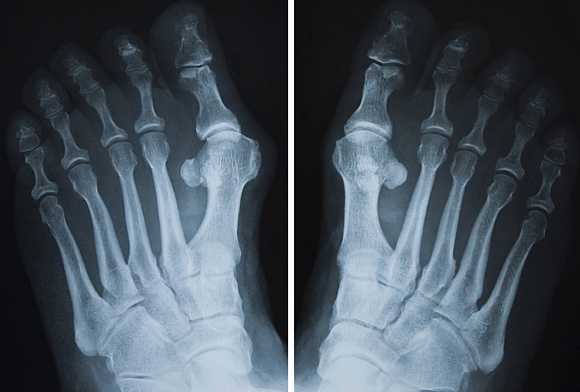

Рентген пальца ноги

Требуемая для исследования конечность - нога - обнажается и ставится на специальную подставку. В некоторых случаях снимок делается с нагрузкой. Для этого пациент поднимает здоровую ногу вверх, сгибая ее в колене, чтобы вес тела приходился на исследуемую ногу.

Рентген пальцев ног или стопы часто проводится в нескольких проекциях, это позволит врачу получить максимальное количество информации о характере повреждения или течении патологического процесса.